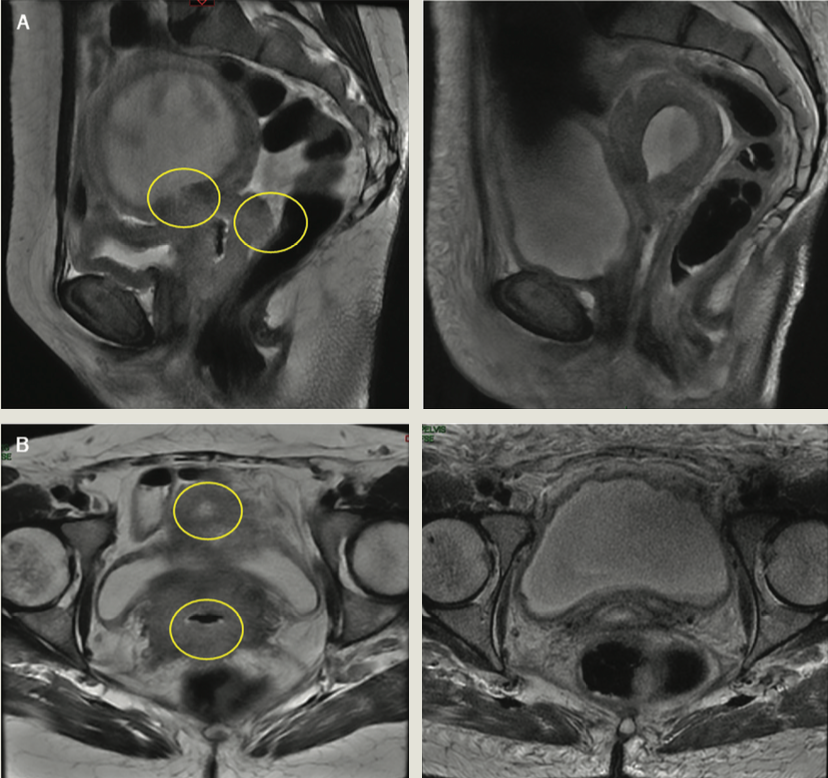

Eight weeks after the end of brachytherapy, a clinical response assessment demonstrated a complete response; however, both the PET-CT and MRI imaging revealed a partial response, as shown in Figures 2 and 3. In addition, the cervical cytology analysis revealed reactive cell changes associated with RT, and a vaginal dome biopsy evidenced extensive necrosis without viable cells in the sample. The patient is currently in a 24-month disease-free period and under surveillance by the medical oncology department.

FIGURE 2. Response Assessment Imaging (A) Pelvic MRI image (sagittal section, without contrast). The image on the left corresponds to the baseline diagnosis; the image on the right corresponds to the response assessment 8 weeks after treatment completion. (B) Pelvic MRI image (axial section, without contrast). The image on the left corresponds to the baseline diagnosis; the image on the right corresponds to the response assessment 8 weeks after treatment completion.